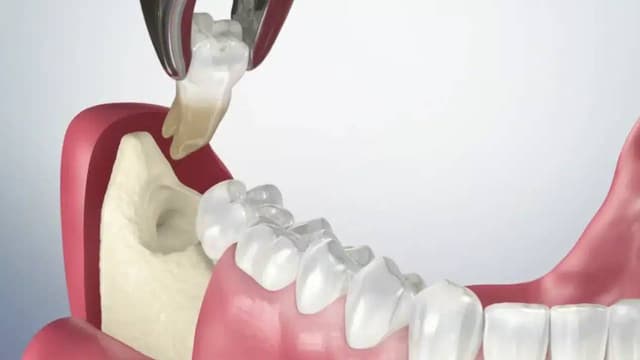

nhổ răng khôn

Trang chủ/nhổ răng khôn